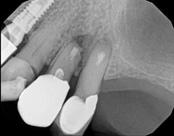

In this situation, some would say the canals are so “calcified” that root canal treatment can’t be done; or sometimes the canal can’t be found. And because of that the tooth would need an extraction and an implant. In some instances, root canal therapy can’t be done but that does not mean the tooth is a loss. The solution is micro-apical surgery, an apicoectomy.